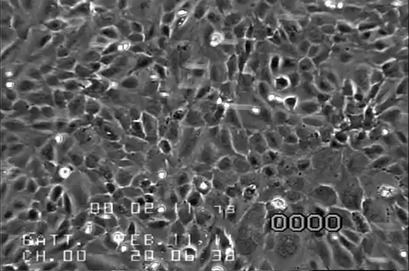

肺內皮細胞 (HPMEC) 的相差和熒光顯微鏡觀察

640-11.png

人肺微血管內皮細胞(HPMEC)的相差上)和熒光顯微鏡(下)。72 小時后,使用ibidi泵系統(右)進行靜態培養(左)和2.3dym/cm²的流動培養。綠色:β-肌動蛋白,紅色=VE-鈣粘蛋白,藍色=DAPI。數據來自德國柏林羅伯特科赫研究所的Daniel Bourquain。